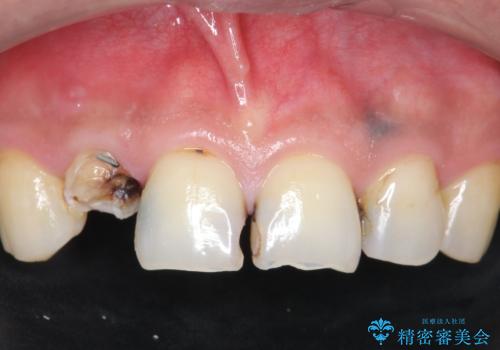

「 放置した虫歯 」 前歯セラミック治療

- 前歯の虫歯に気付きながらも放置し、一念発起し治療を希望され来院されました。

虫歯のマイクロスコープによる丁寧な除去、根管治療、深い虫歯に対する挺出(エクストリュージョン)および歯周外科を行ったのち精度の高いセラミッククラウン製作治療を計画します。

虫歯の放置により、根管治療や深い虫歯に対する処置が必要になりましたが丁寧に一つづつ処置を行ったことで抜歯をすることなく歯を残すことができました。